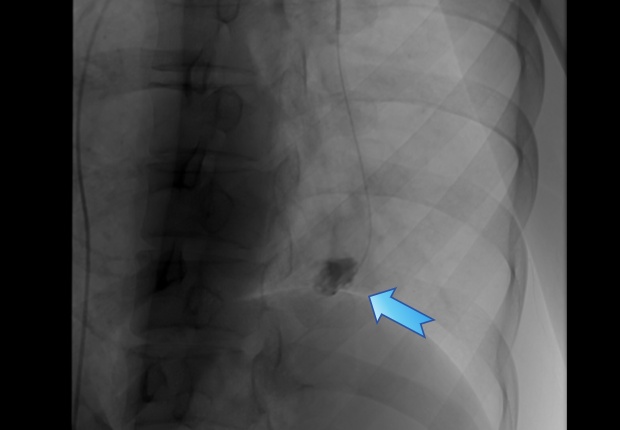

在手术室和麻醉科的支持下,瑞金医院血管微创介入治疗团队为王女士实施介入手术:由王忠敏主任医师主刀、王子寅副主任及单群刚主治医师担任助手,从股静脉穿刺建立通道,在影像引导下将导管逐级送入左肺下叶病变分支,完成超选择性插管,造影清晰显示动脉瘤轮廓与供血。确认定位后,于瘤腔内精准释放多枚解脱弹簧圈,阻断瘤内血流。复查造影未见残余充盈,提示出血风险已被当场解除。整个过程不开胸、不切肺,体表仅有一个微小穿刺点。

经过超选择性插管,完整显示动脉瘤轮廓与供血